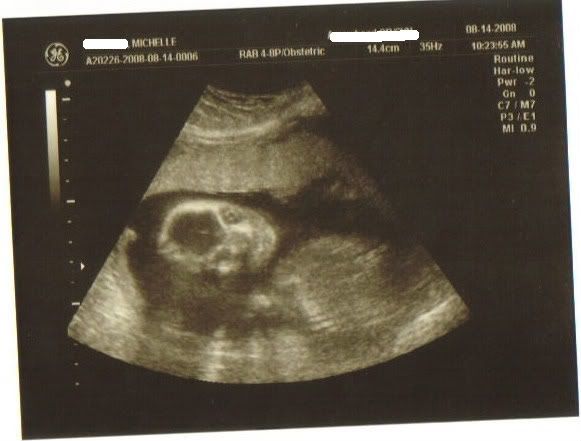

Here he is